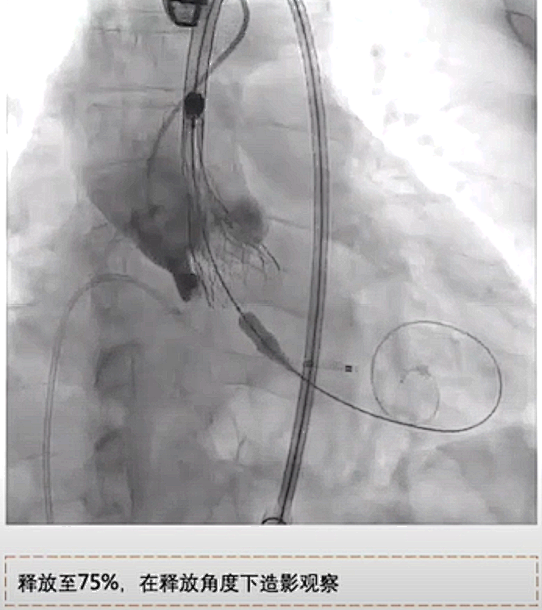

术中采取全麻经右侧股动脉入路,23mm球囊预扩张,瓣膜计划植入深度为瓣下0-1mm,当瓣膜释放至75%时,停止释放观察瓣膜移位情况,发现瓣膜出现轻度位移。

图片

回收后重新定位释放,释放至75%,再次观察,瓣膜位置稳定,完全释放。瓣膜释放后造影发现瓣膜扩张不充分,反流明显,采用23mm球囊后扩张。最终造影轻度瓣周漏,无冠窦处植入深度接近零度,冠脉血流灌注正常。